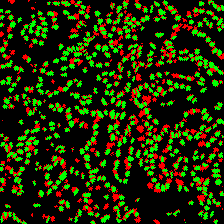

Microscopic image segmentation is a challenging task, wherein the objective is to assign semantic labels to each pixel in a given microscopic image. While convolutional neural networks (CNNs) form the foundation of many existing frameworks, they often struggle to explicitly capture long-range dependencies. Although transformers were initially devised to address this issue using self-attention, it has been proven that both local and global features are crucial for addressing diverse challenges in microscopic images, including variations in shape, size, appearance, and target region density. In this paper, we introduce SA2-Net, an attention-guided method that leverages multi-scale feature learning to effectively handle diverse structures within microscopic images. Specifically, we propose scale-aware attention (SA2) module designed to capture inherent variations in scales and shapes of microscopic regions, such as cells, for accurate segmentation. This module incorporates local attention at each level of multi-stage features, as well as global attention across multiple resolutions. Furthermore, we address the issue of blurred region boundaries (e.g., cell boundaries) by introducing a novel upsampling strategy called the Adaptive Up-Attention (AuA) module. This module enhances the discriminative ability for improved localization of microscopic regions using an explicit attention mechanism. Extensive experiments on five challenging datasets demonstrate the benefits of our SA2-Net model. Our source code is publicly available at \url{https://github.com/mustansarfiaz/SA2-Net}.